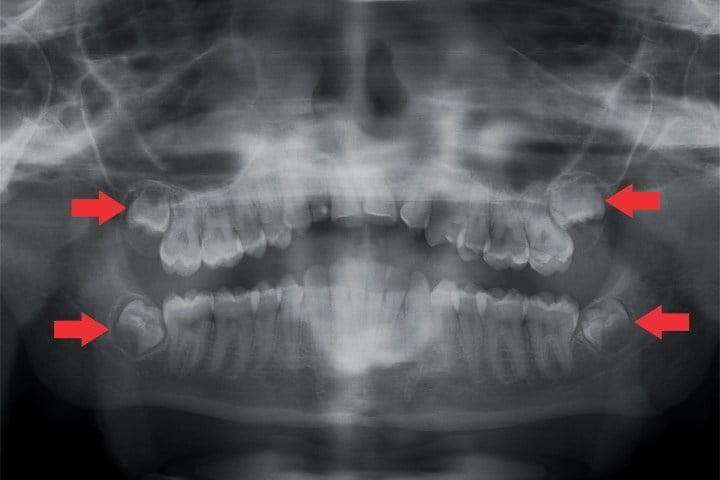

O primeiro passo do tratamento é a realização de exame radiográfico que mostre o exato posicionamento dos dentes. Em princípio, realiza-se uma radiografia panorâmica e eventualmente uma tomografia computadorizada.